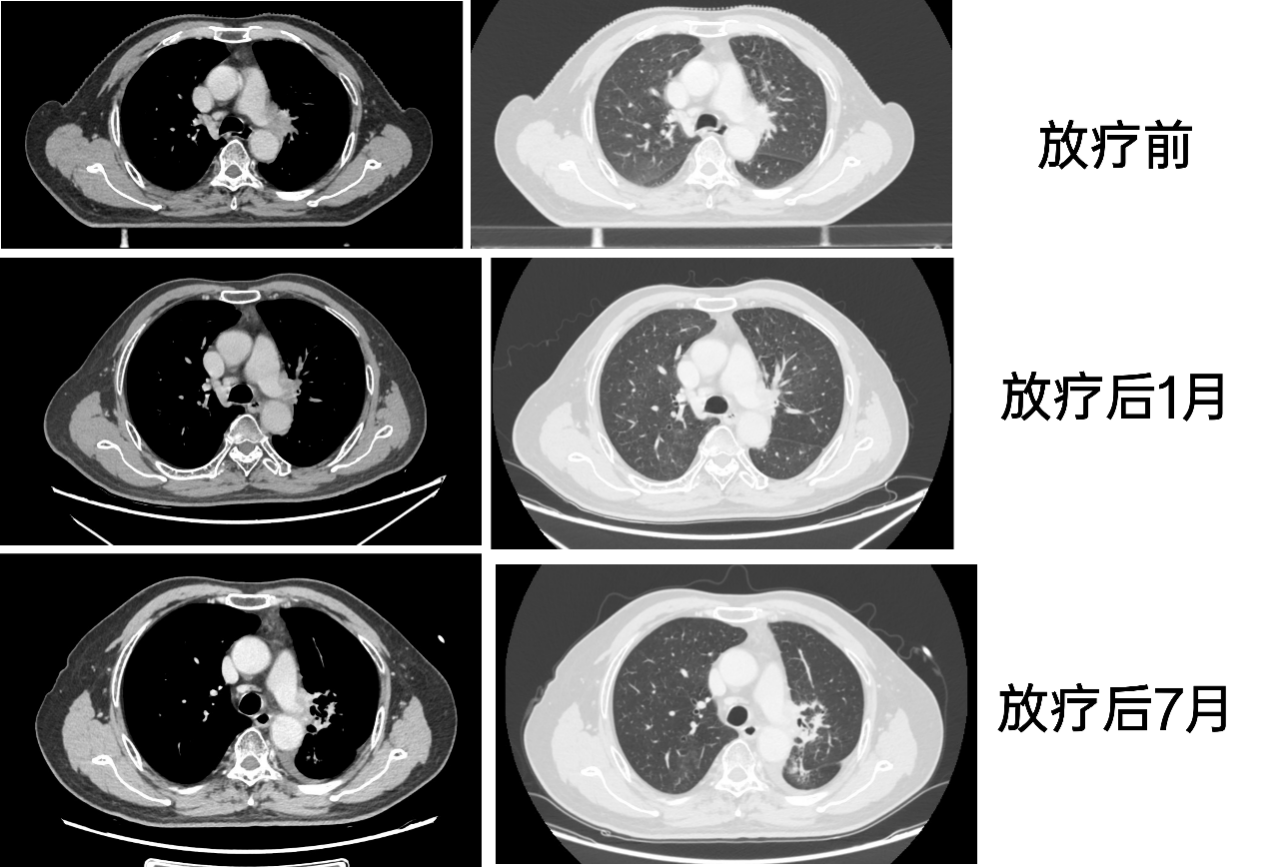

2024-9,放疗后1月,颈胸腹盆CT示:左侧中央型肺癌并左肺门、纵隔淋巴结转移综合治疗后(肿块较前缩小)。

2025-3,放疗后7月,颈胸腹盆CT示:左侧中央型肺癌并左肺门、纵隔淋巴结转移综合治疗后(大致同前)。

2024-6(放疗前)、2024-9(放疗后1月)与2025-3(放疗后7月)CT影像如下: